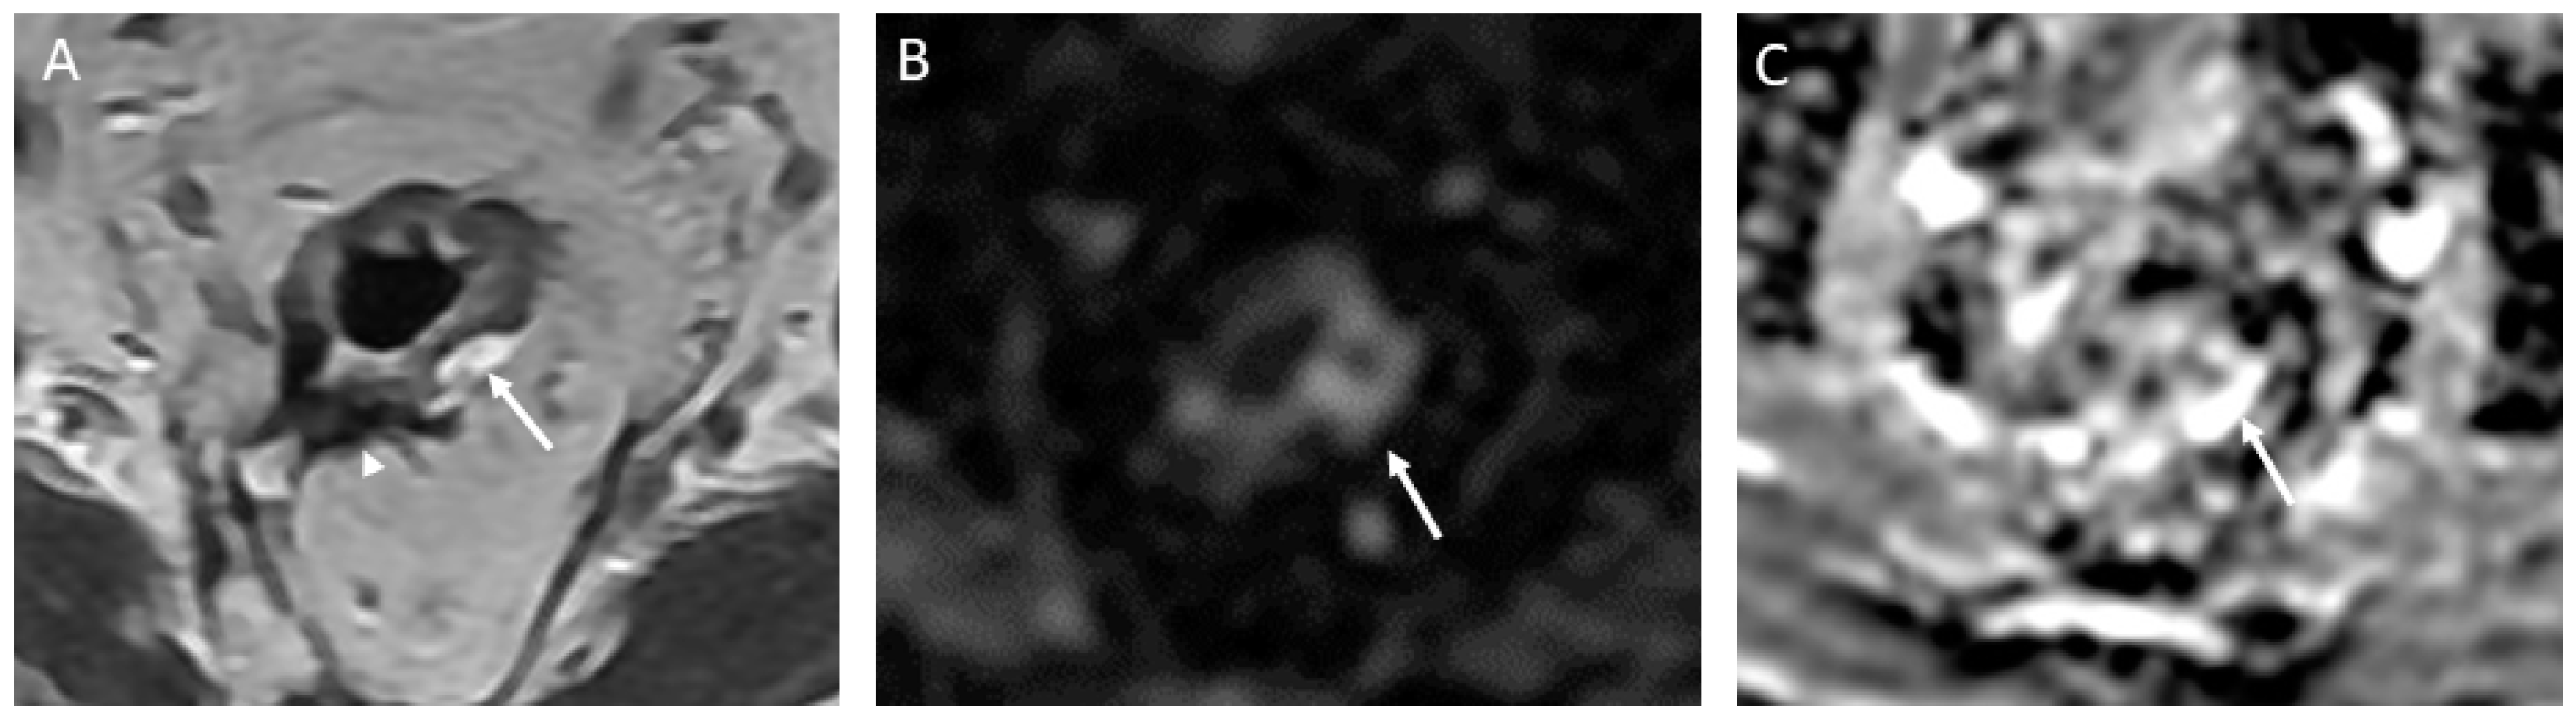

- CR signifies the remarkable disappearance of T2 intermediate signal, indicating a significant reduction in tumor size and suggesting a highly favorable response to treatment. Changes in T2-weighted imaging and DWI pertaining to CR are described below and exemplified in Figure 2:

- T2-weighted imaging—In T2-weighted imaging, CR can be represented as a linear or crescent-shaped scar within the mucosal/ submucosal layers or even the normalization of the rectal wall. It is known that rectal wall normalization can be seen in 5% of cases and is suggestive of CR [64].

- DWI—CR on DWI is characterized by the absence of high signal intensity on high b-value DW images [65,66,67,68]. It is essential to compare DW images at restaging with baseline images and with the normal rectum as references. This can be especially valuable in identifying CR in small, subcircumferential scars [69].